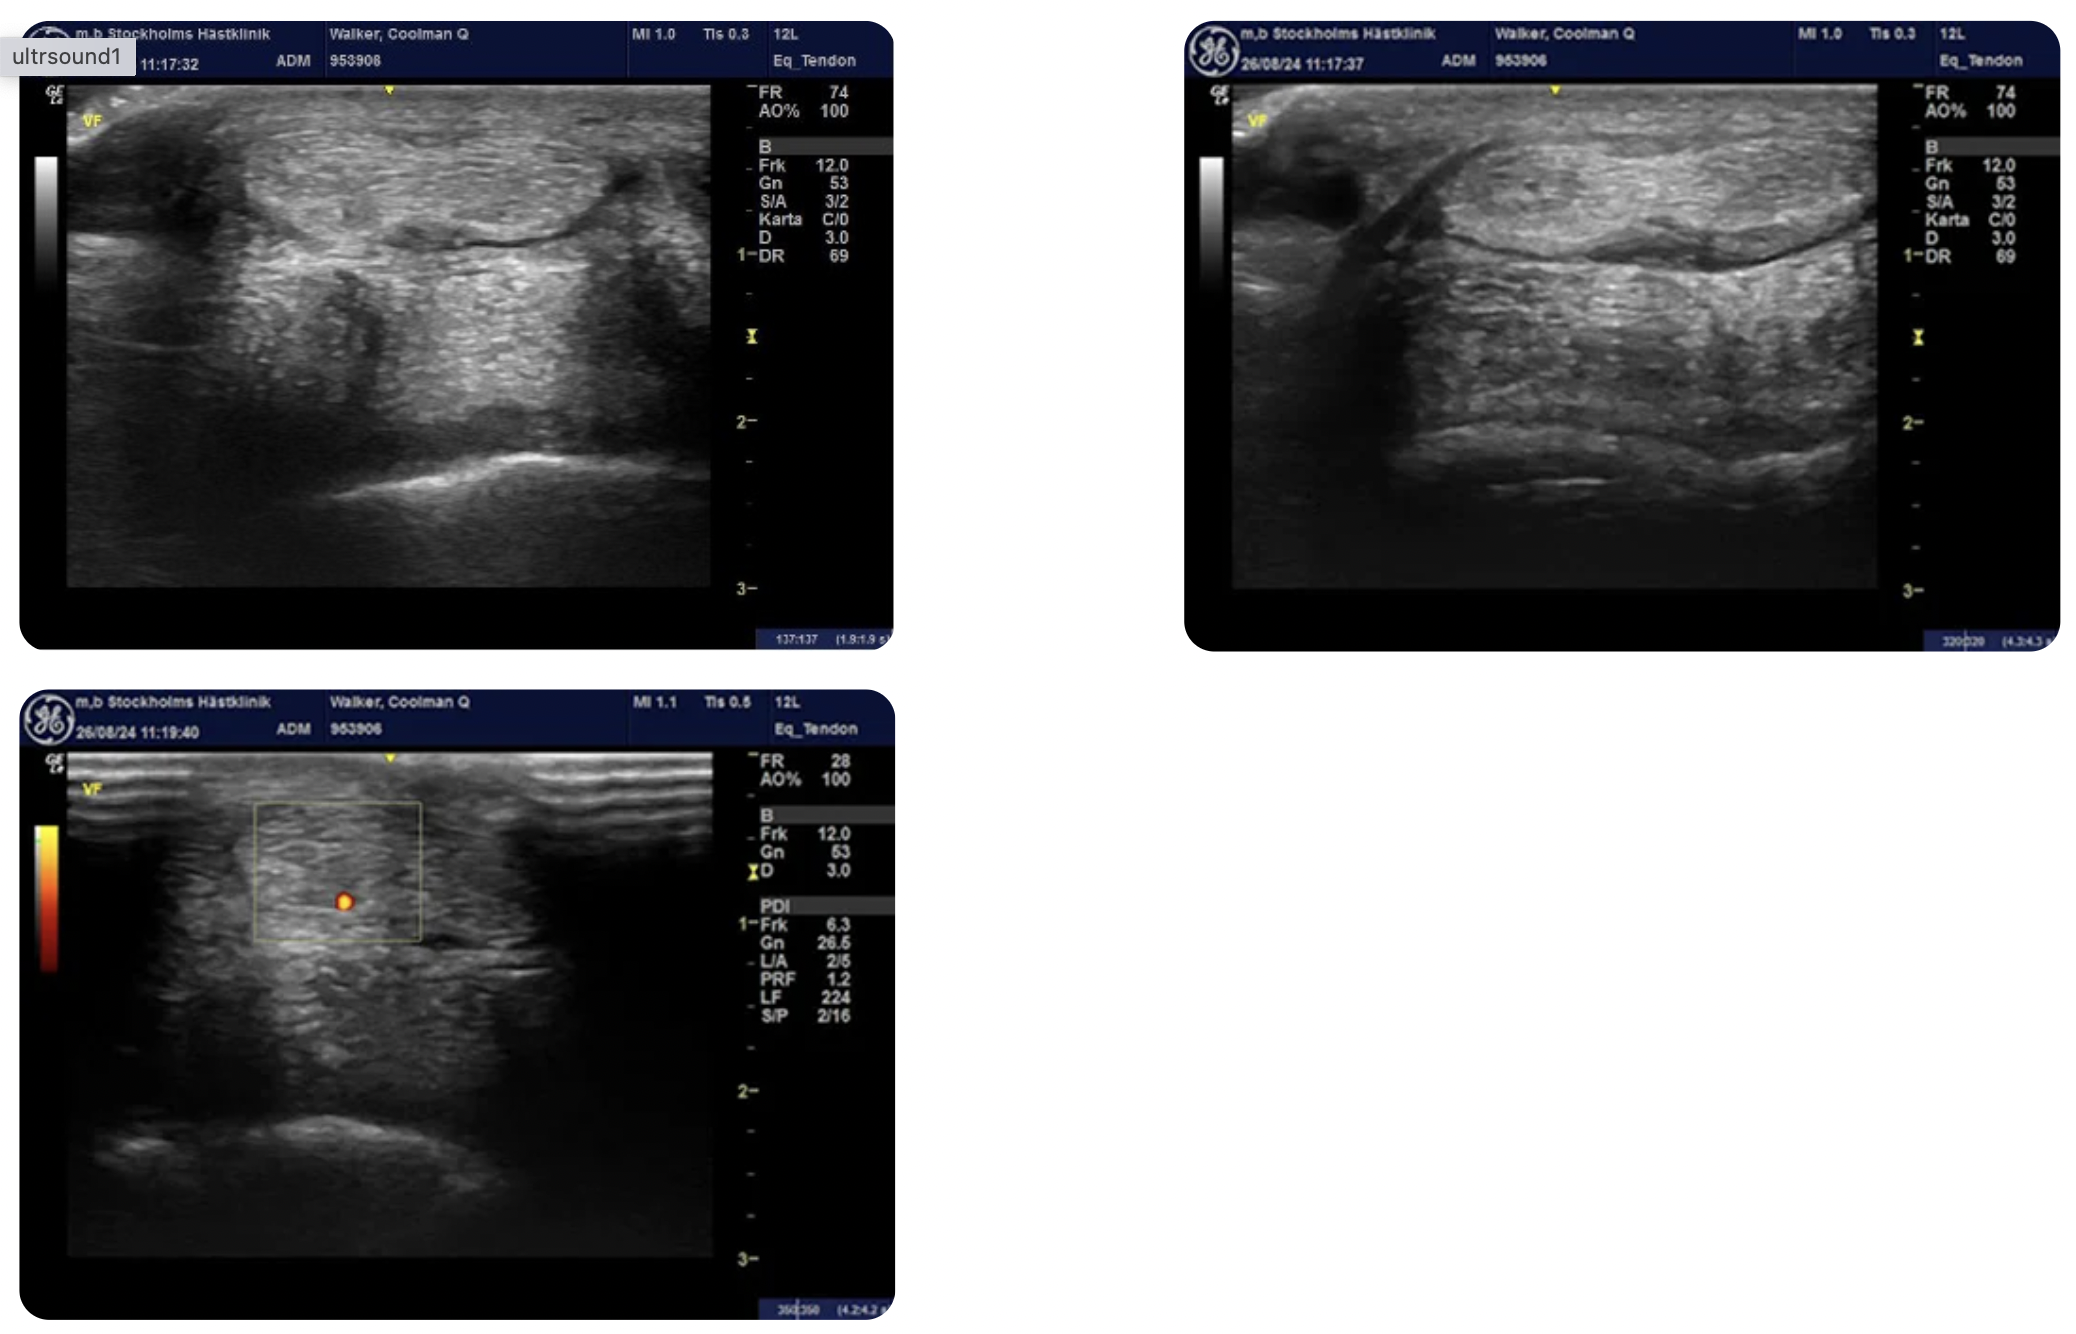

Upon examination with X-ray and ultrasound, Coolman Q was found to have a bulging medial lobe of the distal deep digital flexor tendon (DDFT) with a hypoechoic lesion on the palmar aspect at the level of P1. A positive Doppler signal was detected in the corresponding area as well as in the distal aspect of the DDFT, where the signal was more dorsally evident.

X-rays revealed mild synovial invaginations of the navicular bone, particularly on the medial aspect, along with slight remodeling of the palmar part of the navicular bone and a mild-to-moderate osteophyte on the proximal P1.The DDFT lesion was considered the most clinically relevant finding. Coolman Q was referred for an MRI of the left forelimb to assess the extent of the lesion.